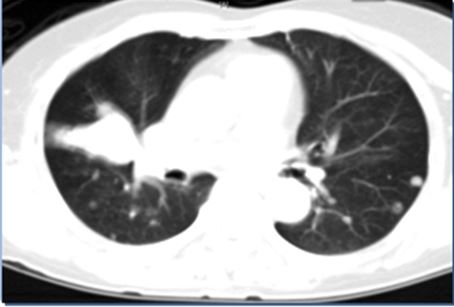

Hình ảnh CT ngực trước và sau điều trị

Trước điều trị                                 Sau 10 tháng

Trước điều trị: Hình ảnh u phân thùy giữa phổi phải. Kích thước 3 x 4 cm. Có nhiều nốt di căn ở cả hai bên phổi.

Sau điều trị: Đáp ứng gần hoàn toàn, u nhỏ đi nhiều và số lượng các ổ di căn hai bên phổi giảm nhiều.